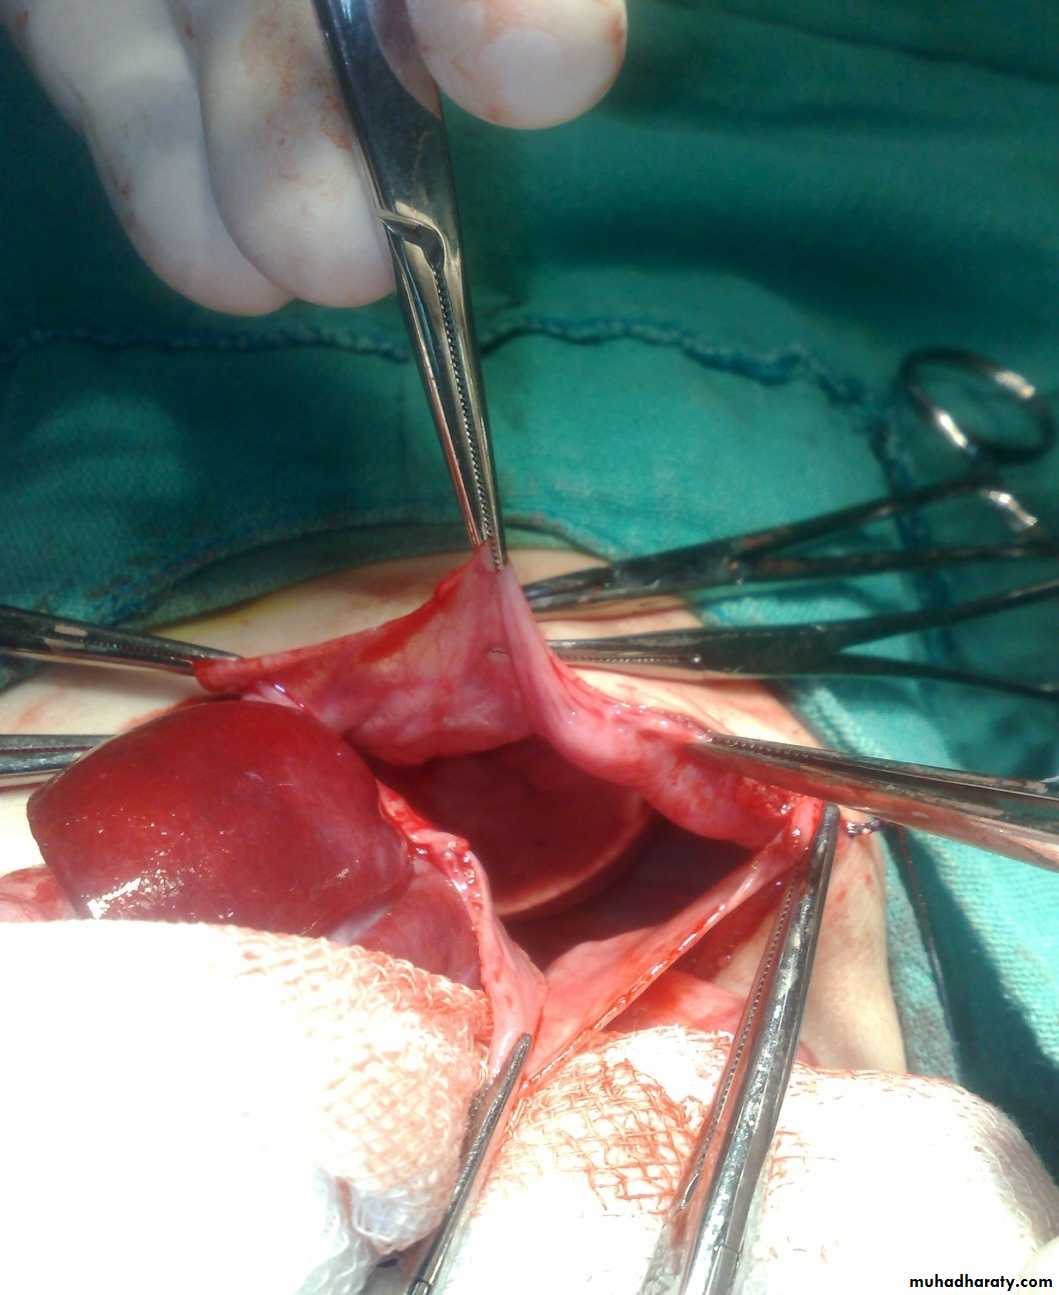

Subcostal incision

content

Defect=sac